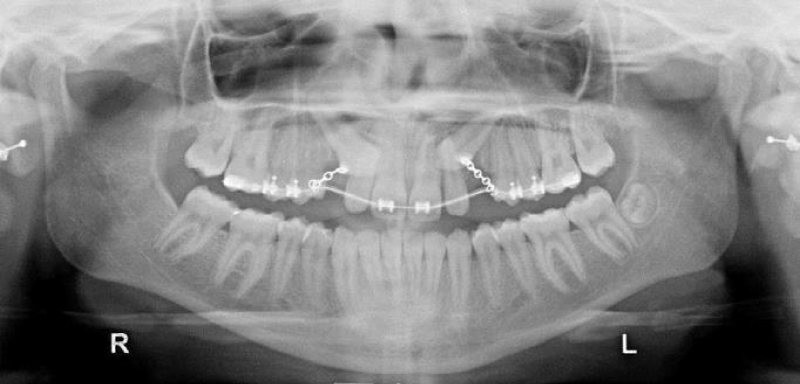

A fixed superior appliance was applied. The oral surgeon performed the surgical exposure of the impacted teeth and the orthodontist attached an auxilliary button directly to the crown’s enamel on the palatal side. This one-step approach is preferable, and to assure good bonding to the enamel the exposure should be the least traumatic possible. A fibrine sponge is useful to reduce the bleeding around the crown, and a periodontal curette can be used to remove the primary cuticle from the enamel. An orthophosphoric acid (37 %) was used for 40 second and the button was bonded. A ligature with several holes was prepared and attached to the button before bonding (Figure 2a).

The surgical exposure was very conservative. Only the bony tissue over the crown was excised and the flap completely sutured. We consider this light surgical exposure to be beneficial to the future periodontal health.

After a week the suture and the surgical dressing were removed, and light orthodontic force (no more 60 grams/2 ounces) with elastic ligatures was started. Concurrently sufficient space was created in the arch thus reducing the diastema. A preformed round arch wire 0.020 was used to provide sufficient stiffness (Figure 2b-c).